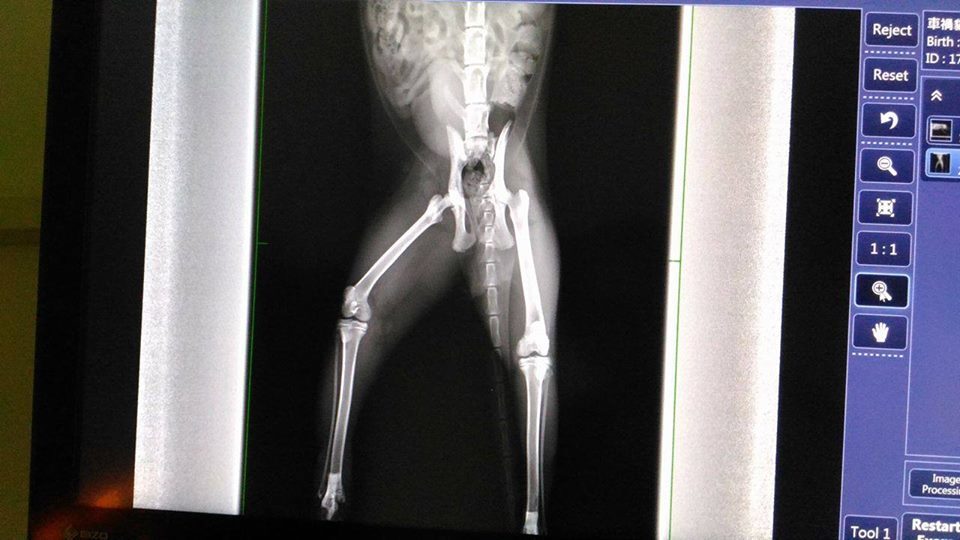

- 編號: 7702

主題: 因車禍而住院看護的車禍貓小智 申請者姓名: 臺北市支持流浪貓絕育計劃協會 花色: 申請日期: 2017-06-09 17:28:31 申請者部落格: 申請者臉書網址: 所在縣市/合作醫院: 台北市/澄諾動物醫院 治療費用: 7245元 需求人數: 17人 已結案 (2024-06-01 13:27:19) 報名人員: Helen Yu(已付款)、Sophia Kuo(已付款)、SKY x15(已付款)、 候補人員: 動物病情說明: 親人、撒嬌、愛討摸摸抱抱的超可愛小小蒜頭鼻,小智

來自106年5月中旬,

志工執行完TNR回置作業時,

行經夜市,

發現一跛行小貓,

詢問餵養的攤販得知,

貓咪於前一天被摩托車撞到、拖行,

因為店家生意忙碌,

也沒時間去觀察街貓狀況,

這一群小貓共有三兄弟生活在夜市攤商水溝暗巷中,

一個月前已由附近志工抓紮絕育。

受傷的小智,

是三兄弟中最親人的一隻,

但被車撞到後,

一整天都不敢靠近餵食區吃飯,

接近夜市打烊時,

在餵養攤販的協助下,

順利抓到親人的小虎斑,

隔日送醫,

可發現腳痛難耐,

但仍不敢反抗,

雖然剛開始在醫院治療時有飛竄躲起來,

不過都不會出手攻擊。

腳的骨頭沒有什麼問題,下週回診看傷口狀況如何,就可原放~